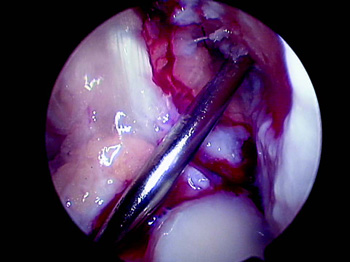

Creemos que el gran aporte de la cirugía con doble banda ha sido analizar el control rotacional, hecho que podemos lograr con una banda al reubicar la inserción femoral en un punto más a las 3 o a las 9 del reloj horario, existen muchas publicaciones que lo avalan (19, 20, 21). Musahl (22) muestra en su estudio que los túneles femorales dispuestos en forma más horizontal aportan mejor control rotacional. La tendencia actual es ubicar el túnel femoral más horizontal, remedando la huella de inserción del LCA, lo cual se puede lograr utilizando un portal anteromedial, que en nuestra experiencia utilizamos poco, como también medializando el túnel tibial y redirec-cionándolo con una dilatación mínimo de 2 mm (Fig. 1). Con esto logramos llegar de una forma más horizontal a la pared femoral obteniendo así un mejor control rotacional. (Figs. 2 y 3).

Figura 2: Visión artroscópica de colocación de aguja guía femoral transportal tibial, en posición anatómica. |